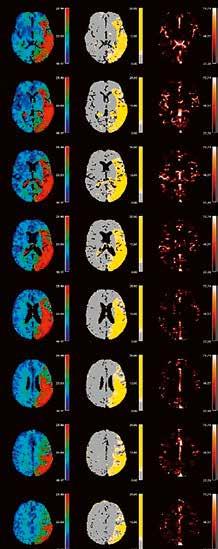

2. Vergleich eines cranialen CTs mit und ohne Deep Learning Rekonstruktion AiCE:

CTDI

30,2 mGy 544,6 mGy*cm

Felsenbein-CT Felsenbein CT-Rekonstruktion

Elektrode

CCT AIDR

der

Felsenbein-DVT

CCT AiCE

Vergleich

DVT: CDTI DLP Volumen-CT 6,5 mGy 39 mGy*cm DVT 7,3 mGy 76,6 mGy*cm Vorgänger-CT 17,1 mGy 176 mGy*cm CT vs. DVT

„AiCE unterstützt die Diagnosefindung in der Neuroradiologie dank der sofort sichtbar besseren Bildqualität bei gleicher Dosis.“

1.

einer Felsenbeinaufnahme, CT vs.

VISIONS 31 // 19 © 2021 C ANON MEDICAL SYSTEM S

DLP

Dosis

Unterschiedliche Color-Maps mit eindeutigen Infarktzeichen der linken Hirnhälfte.

Eindeutige Visualisierung des Infarktkerns (rot) sowie der Penumbra (gelb). Zusätzlich werden die Volumina, das Mismatch Ratio und das Relative Mismatch dargestellt.

rBV MTT rBF TMAX tMIP TTP